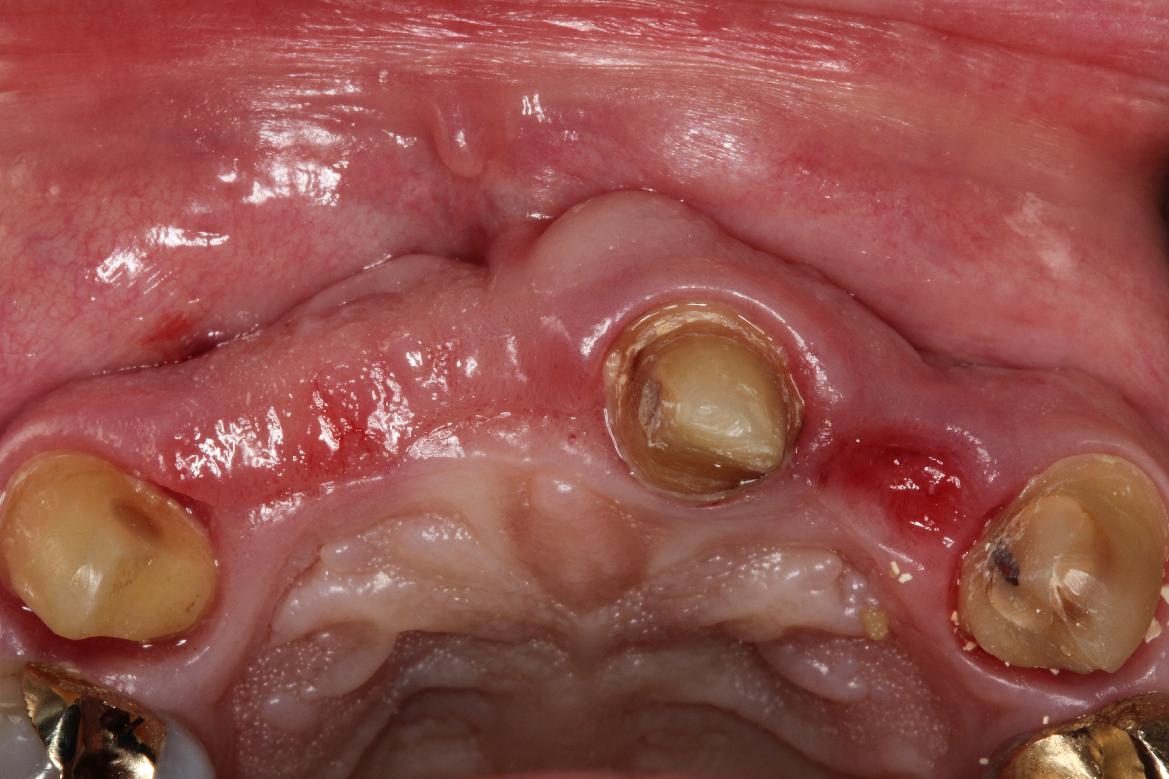

5/5 - Post-operative healing at 3 monthsPre-prosthetic soft tissue augmentation of the ridge contour with mucoderm®- Dr. F. Rathe